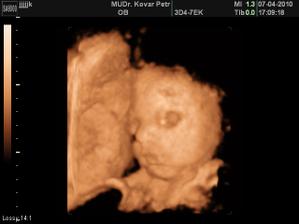

Naše milované miminko

v červnu 2010 se nám narodí naše první mimi..Jsme moc šťastní. A bude to malá princezna!!!